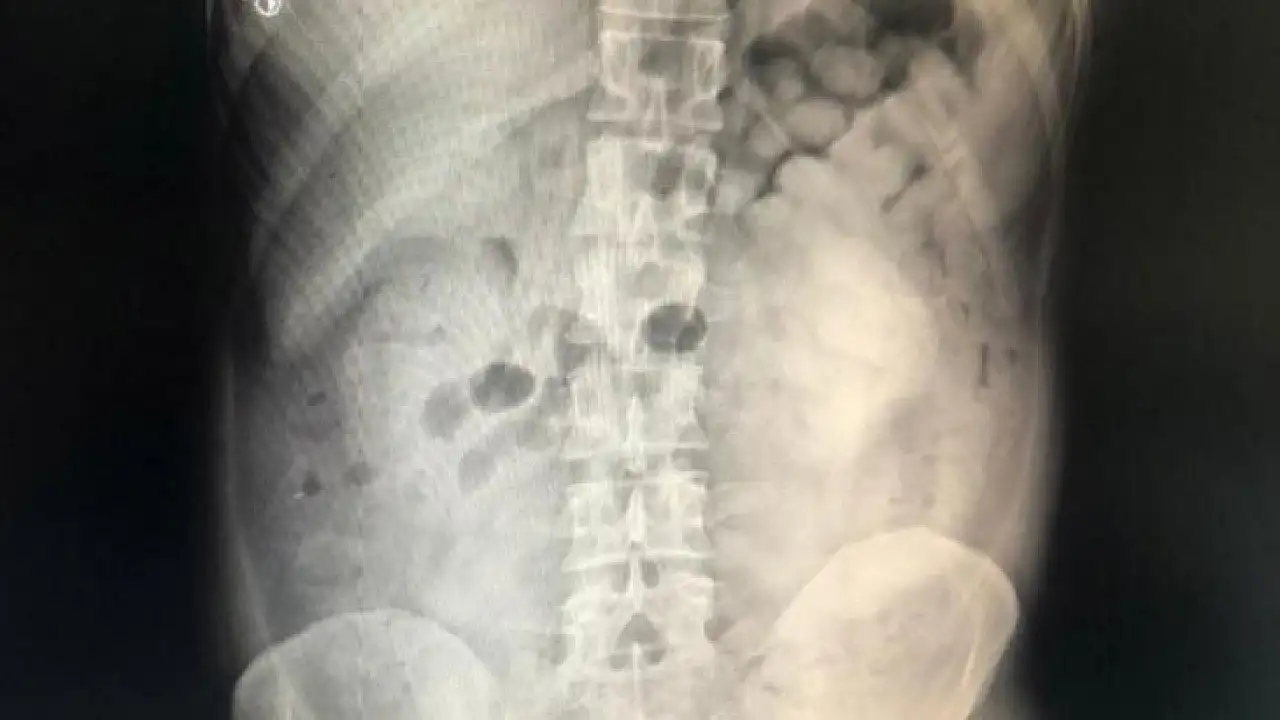

Doktor muayenesi ve çekilen film sonucunda şüphelinin sindirim sisteminde 800 gram eroin maddesi ele tespit edildi.